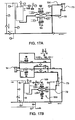

- Fig. 1 is a schematic representation of a hemodialysis system.

- the system 5 includes two flow paths, a blood flow path 10 and a dialysate flow path 20.

- Blood is drawn from a patient.

- a blood flow pump 13 causes the blood to flow around blood flow path 10, drawing the blood from the patient, causing the blood to pass through the dialyzer 14, and returning the blood to the patient.

- the blood may pass through other components, such as a filter and/or an air trap 19, before returning to the patient.

- anticoagulant may be supplied from an anticoagulant supply 11 via an anticoagulant valve 12.

- a dialysate pump 15 draws dialysate from a dialysate supply 16 and causes the dialysate to pass through the dialyzer 14, after which the dialysate can pass through a waste valve 18 and/or return to the dialysate feed via dialysate pump 15.

- a dialysate valve 17 controls the flow of dialysate from the dialysate supply 16.

- the dialyzer is a type of filter having a semi-permeable membrane, and is constructed such that the blood from the blood flow circuit flows through tiny tubes and the dialysate solution circulates around the outside of the tubes. Therapy is achieved by the passing of waste molecules (e.g., urea, creatinine, etc.) and water from the blood through the walls of the tubes and into the dialysate solution. At the end of treatment, the dialysate solution is discarded.